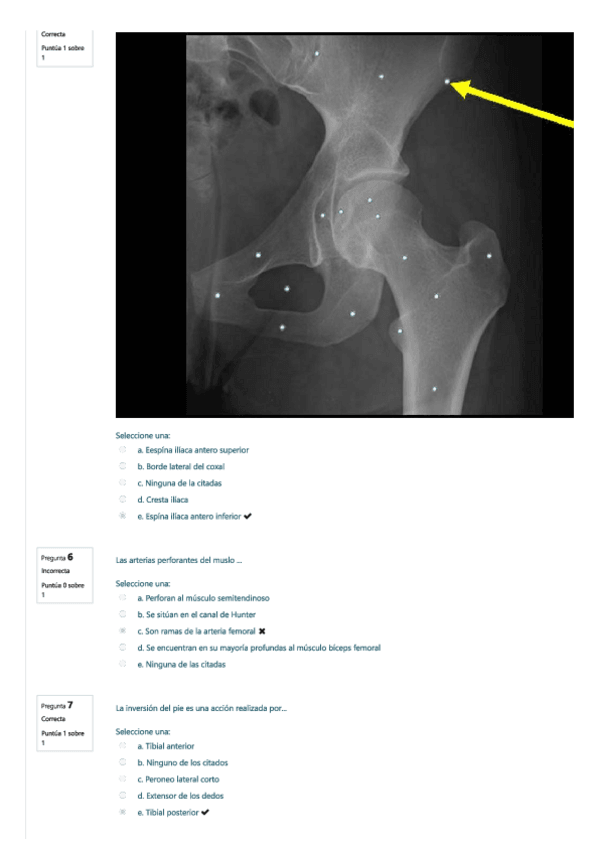

He publicado nuevos test de 1º Anatomía Humana Básica: AUTOEVALUACION-2020.pdf

18 páginas

He publicado nuevos examenes de 1º Anatomía Humana Básica: EXAMEN-AHB-SEPTIEMBRE-2020.pdf

12 páginas